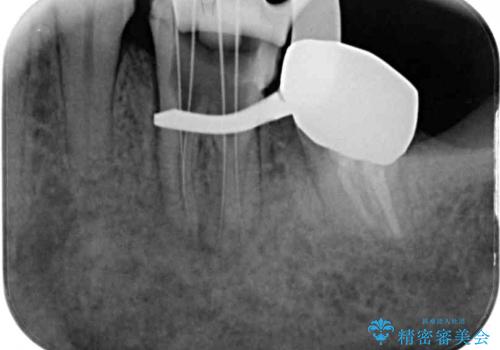

根管治療を行う上で、ラバーダム防湿は処置の中で最も重要な要素です。

左下奥歯は、前医より難治性なので抜歯も考えるよう言われたそうですが、一度もラバーダムを用いた根管治療はされていないとのことでした。

まずは左下奥歯の根管治療を行い、痛みが引いたことを確認してから矯正治療を開始しました。